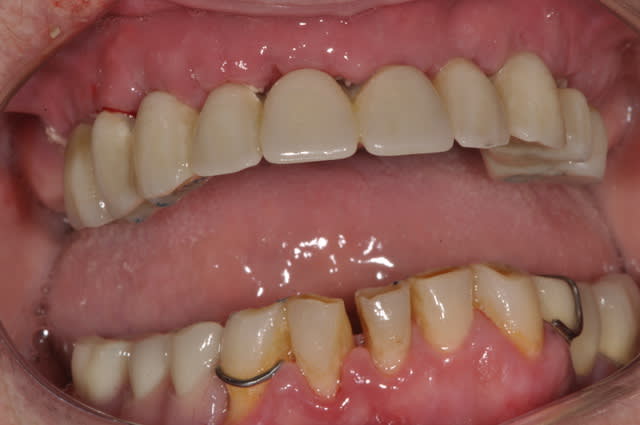

extraction implantation mise en charge immédiate

mandibule

Pr  op e0j5ju - Eugenol